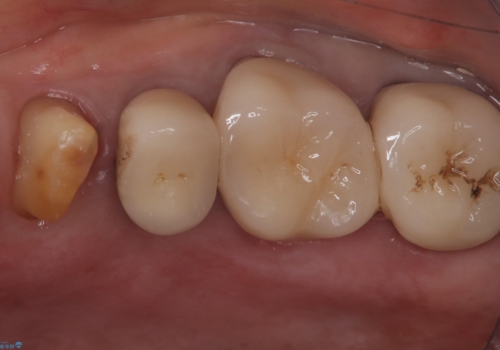

- 主訴:昔入れた被せものの境目の黒いところが気になる

クラウンの不適により境目に汚れが溜まり、黒く見えていました。

古いクラウンを除去し、不適部位から中で広がっていたカリエスを除去したのちCRにて築造、仮歯を経てセラミッククラウンをセットしています。